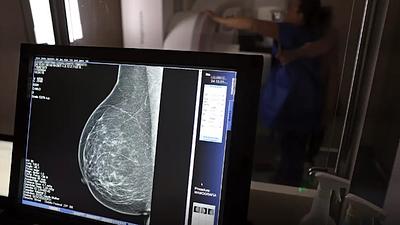

IA antecipa risco de câncer de mama por até cinco anos

Modelo de inteligência artificial analisa mamografias para avaliar risco do desenvolvimento da doença. Técnica pode ajudar a identificar casos não detectados pelo exame tradicional.